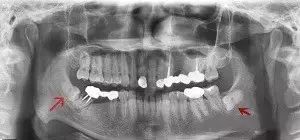

- Among those with erupted wisdom teeth, impaction and misalignment account for about 44%.

- The incidence in the lower jaw is about 2.5 times higher than that in the upper jaw.

This can be seen very clearly on X-rays.

The statement in the article is correct, not all wisdom teeth need to be extracted, as it depends on individual cases. It is best to have an X-ray taken before making a decision.

If they cause repeated pain or impaction, such as tilting forward, backward, horizontally, or inverted, it is better to extract them, even if it is difficult. This is because they cannot grow in properly. Moreover, it is possible that the adjacent teeth in front of it may be affected by inflammation this year, and then extraction of one tooth may require extraction of another later on!